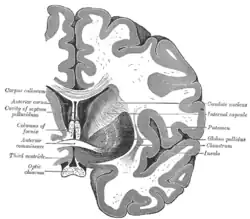

Structure

Along with the putamen, the caudate forms the dorsal striatum, which is considered a single functional structure; anatomically, it is separated by a large white-matter tract, the internal capsule, so it is sometimes also described as two structures—the medial dorsal striatum (the caudate) and the lateral dorsal striatum (the putamen). In this vein, the two are functionally distinct not because of structural differences, but merely because of the topographical distribution of function.

The caudate nuclei are near the center of the brain, sitting astride the thalamus. There is a caudate nucleus in each hemisphere of the brain. Each nucleus is C-shaped, with a wider "head" (caput in Latin) at the front, tapering to a "body" (corpus) and a "tail" (cauda). Sometimes a part of the caudate nucleus is called the "knee" (genu).[7] The caudate head receives its blood supply from the lenticulostriate artery; the tail of the caudate receives its blood supply from the anterior choroidal artery.[8]